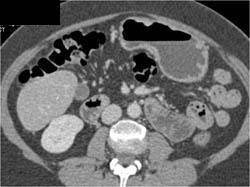

Antral Cancer